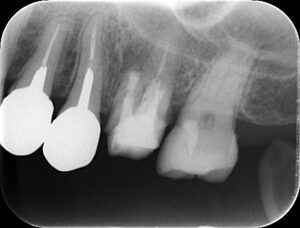

レントゲン写真です。

真ん中あたり、黒くなった丸い部分が病巣です。

炎症により広範囲に骨が溶けています。

別の角度から見たレントゲン写真です。

歯の根の周りに大きな病巣があります。